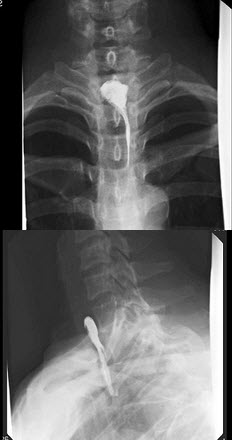

14、单项选择题

男,55岁,左侧舌下肿胀不适2个月余,体检发现左侧舌下肿胀,舌下阜处可见脓苔黏附,触痛,按之可见淡黄色脓液从舌下阜溢出,摄片如图所示,最可能诊断()

A.左侧颌下腺涎石

B.左侧舌下腺涎石

C.左侧腮腺涎石

D.正常影像

E.左侧下颌骨含牙囊肿